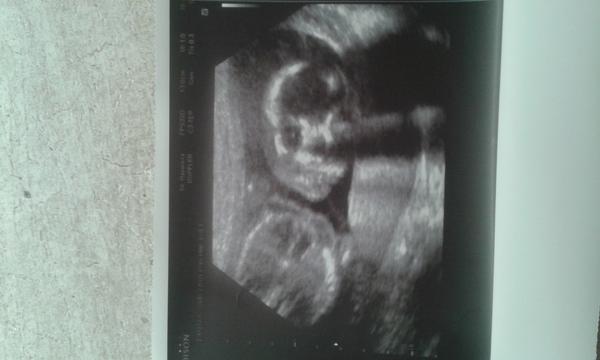

@luccyj toto jsme videli na ultrazvuku na genetice ve 20 tydnu a pani doktorka rekla ze je to klucik. a intuice me zklamala celou dobu jsem byla presvedcena ze je to holcicka 🙂

@jsss krasne viditelny🙂 takhle se mi ukazali pba kluci 🙂

@jsss tady mam utz nalevo syn, napravo nase dcera 🙂